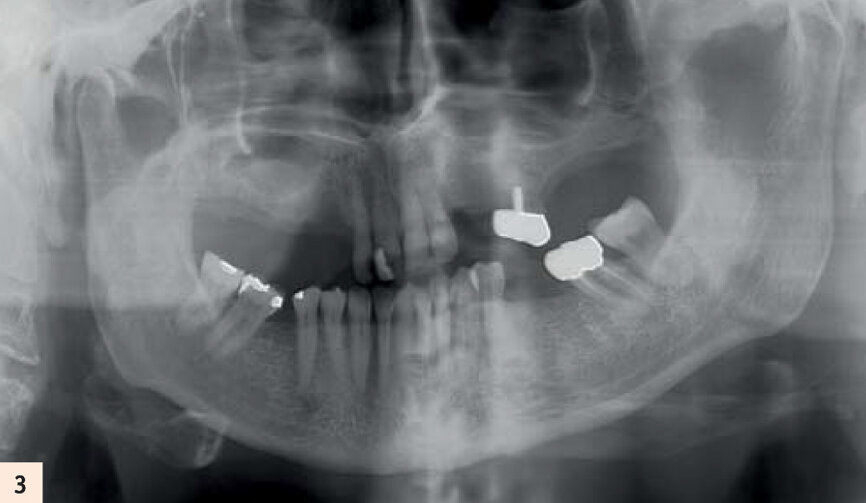

Elle porte un appareil amovible au maxillaire, côtoyant 5 dents naturelles. Elle souhaite une solution fixe (Figs. 1, 2, 3). Après empreintes, mise en articulateur et confection d’un guide radiologique, un examen 3D est réalisé. L’analyse des fichiers DICOM’s transférés sur le logiciel de planification CoDiagnostiX, confirme un faible volume osseux.5Les sinus ont fortement pneumatisé le maxillaire et les parois antérieures sont au niveau des canines.

Radiographie panoramique de la situation initiale.